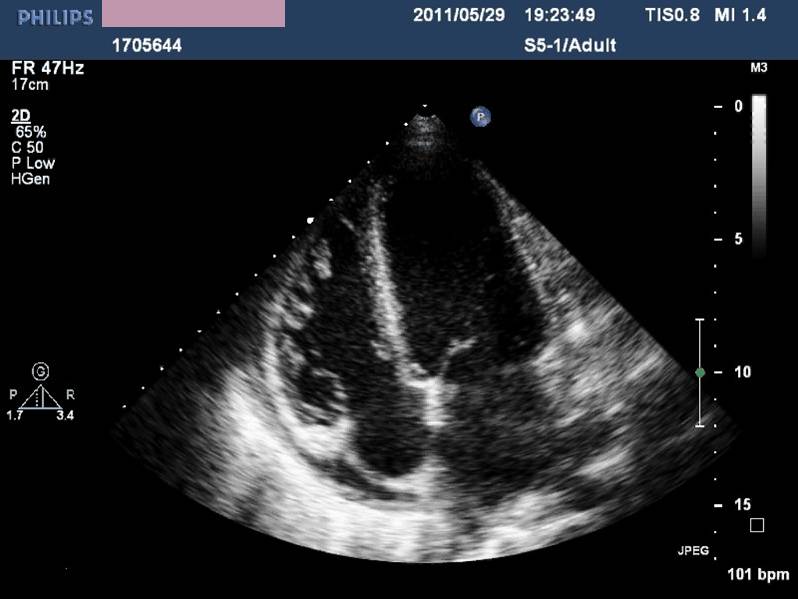

——床旁超声心动:节段性室壁运动异常,左房增大,轻度二尖瓣关闭不全,左室收缩功能减低,LVEF 45%,少量心包积液

现病史-超声心动

急性左心收缩功能不全